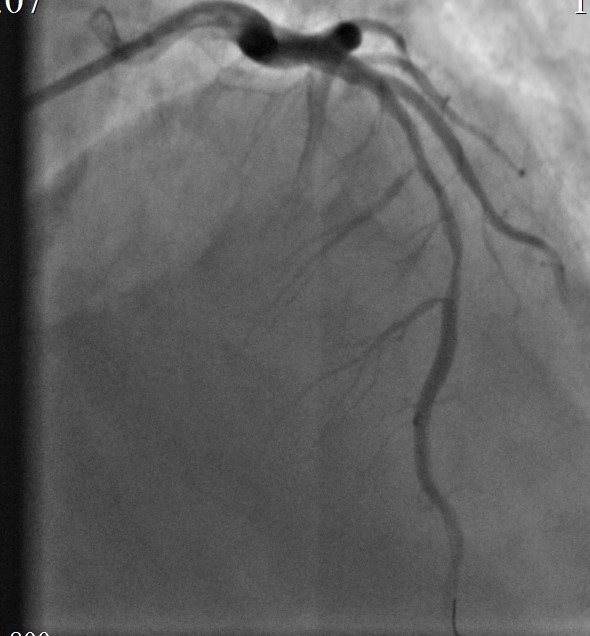

Выполнена баллонная постдилатация стентированного сегмента баллонным катетером 3,5-24мм.

Контрольная КАГ: среднем отделе выраженная экстравазация контраста, (III тип по Ellis – в анатомическую полость).

Произведено временное перекрытие («пломбирование») просвета ПМЖВ « выше зоны стентирования» баллонным катетером 3,5х24,0мм при Р до 6 атм. (10мин). Подготовка к экстренному стентированию «стент-графтом».